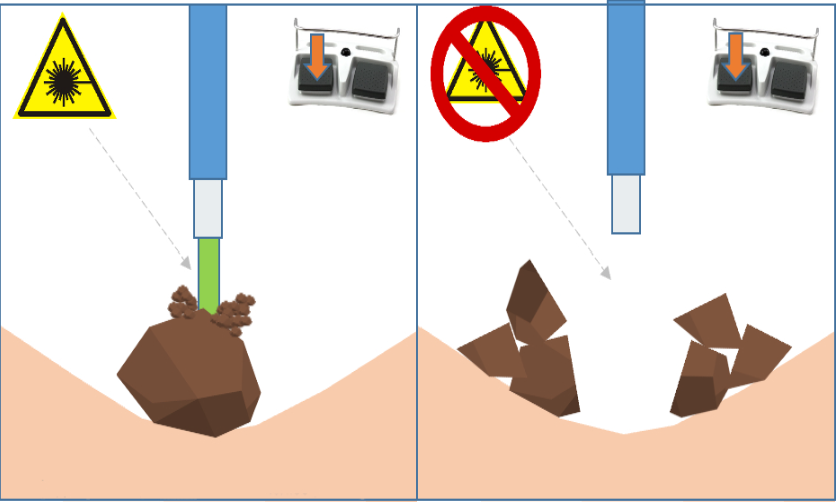

РМК

Принцип работы Tissue sensor заключается в том, что лазер различает какая ткань (твердая или мягкая) находится перед торцом хирургического волокна. Таким образом, при проведении литотрипсии, лазер автоматически останавливает подачу излучения при наведении на слизистую, исключая риск повреждения.

"Детектор ткани" - это инновационная разработка, направленная на абсолютную максимизацию безопасности во время дробления камней. Технология особенно полезна при эндоскопическом лечении мочекаменной болезни.

Благодаря технологии детектирования тканей лазер различает какая ткань (твердая или мягкая) находится перед торцом хирургического волокна. Таким образом, при проведении литотрипсии, лазер автоматически останавливает подачу излучения при наведении на слизистую, тем самым повышая безопасность операции.

Технология позволяет уменьшить риск попадания лазерного излучения на окружающие мягкие ткани во время дробления камней и снизить нагрев окружающей жидкости вследствие “непродуктивных” импульсов, не достигших цели.

Датчик ткани — это инновационная разработка «ИРЭ-Полюс», направленная на абсолютную максимизацию безопасности во время дробления камней. Данная технология призвана усилить развивающийся тренд на эндоскопическое лечение мочекаменной болезни.Принцип работы Tissue sensor заключается в том, что лазер различает какая ткань (твердая или мягкая) находится перед торцом хирургического волокна. Таким образом, при проведении литотрипсии, лазер автоматически останавливает подачу излучения при наведении на слизистую, исключая риск повреждения.

Tissue sensor позволяет достичь высокого уровня безопасности эндоскопического лечения мочекаменной болезни, снижается травматизация тканей во время литотрипсии.

Настройка чувствительности имеет несколько уровней. Это позволяет получить максимально корректное распознавание камней и мягких тканей даже в сложных условиях, например, при плохой видимости, плохом оттоке ирригационной жидкости, повышенной «пыльности» камня, при фрагментации в режиме «попкорнинга» или если дробление с прямым контактом камня и волокна невозможно.